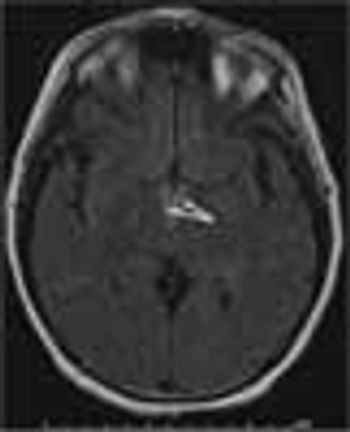

A 26-year-old woman at 30 weeks’ gestation presented to the emergency department with a throbbing frontal headache of 1 month’s duration. She had also had peripheral blurred vision for the past 2 weeks. Acetaminophen initially decreased her pain but was no longer effective. She had had a previous miscarriage.